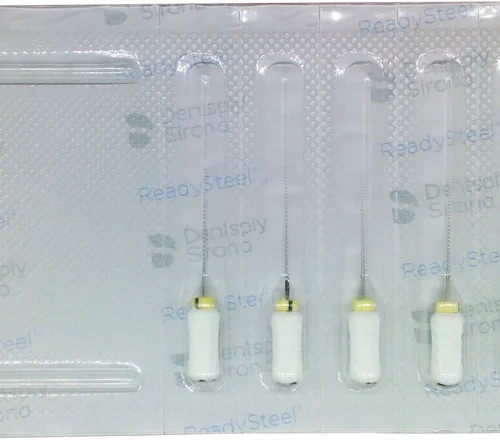

Sterile håndfiler i rustfritt stål.

- Blister med 6 forsteriliserte instrumenter

- Gjensteriliserbare filer

- Tilgjengelig i lengdene 21 mm, 25 mm og 31 mm

- Størrelser fra 006 til 140

- 2 % konisitet

- Godt grep for enkel bearbeiding av kalkede og krummede kanaler